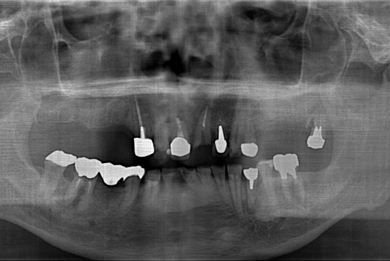

| 性別/年齢 | 男性 / 58歳 | ||||||||||||||||||||||||||||||||

| 治療方針 | 右上奥はソケットリフトにて上顎洞拳上してインプラント埋入を可能にし、上顎前歯部は骨再生法によりインプラント治療を行う。その他、補綴により口腔内全体の機能的審美的回復を行う。 | ||||||||||||||||||||||||||||||||

| 治療内容 | インプラント8本(GBR、ソケットリフト)、ハイブリッドセラミッククラウン17本(セラミック用土台5本) | ||||||||||||||||||||||||||||||||

| 治療期間 | 1年9ヶ月 |